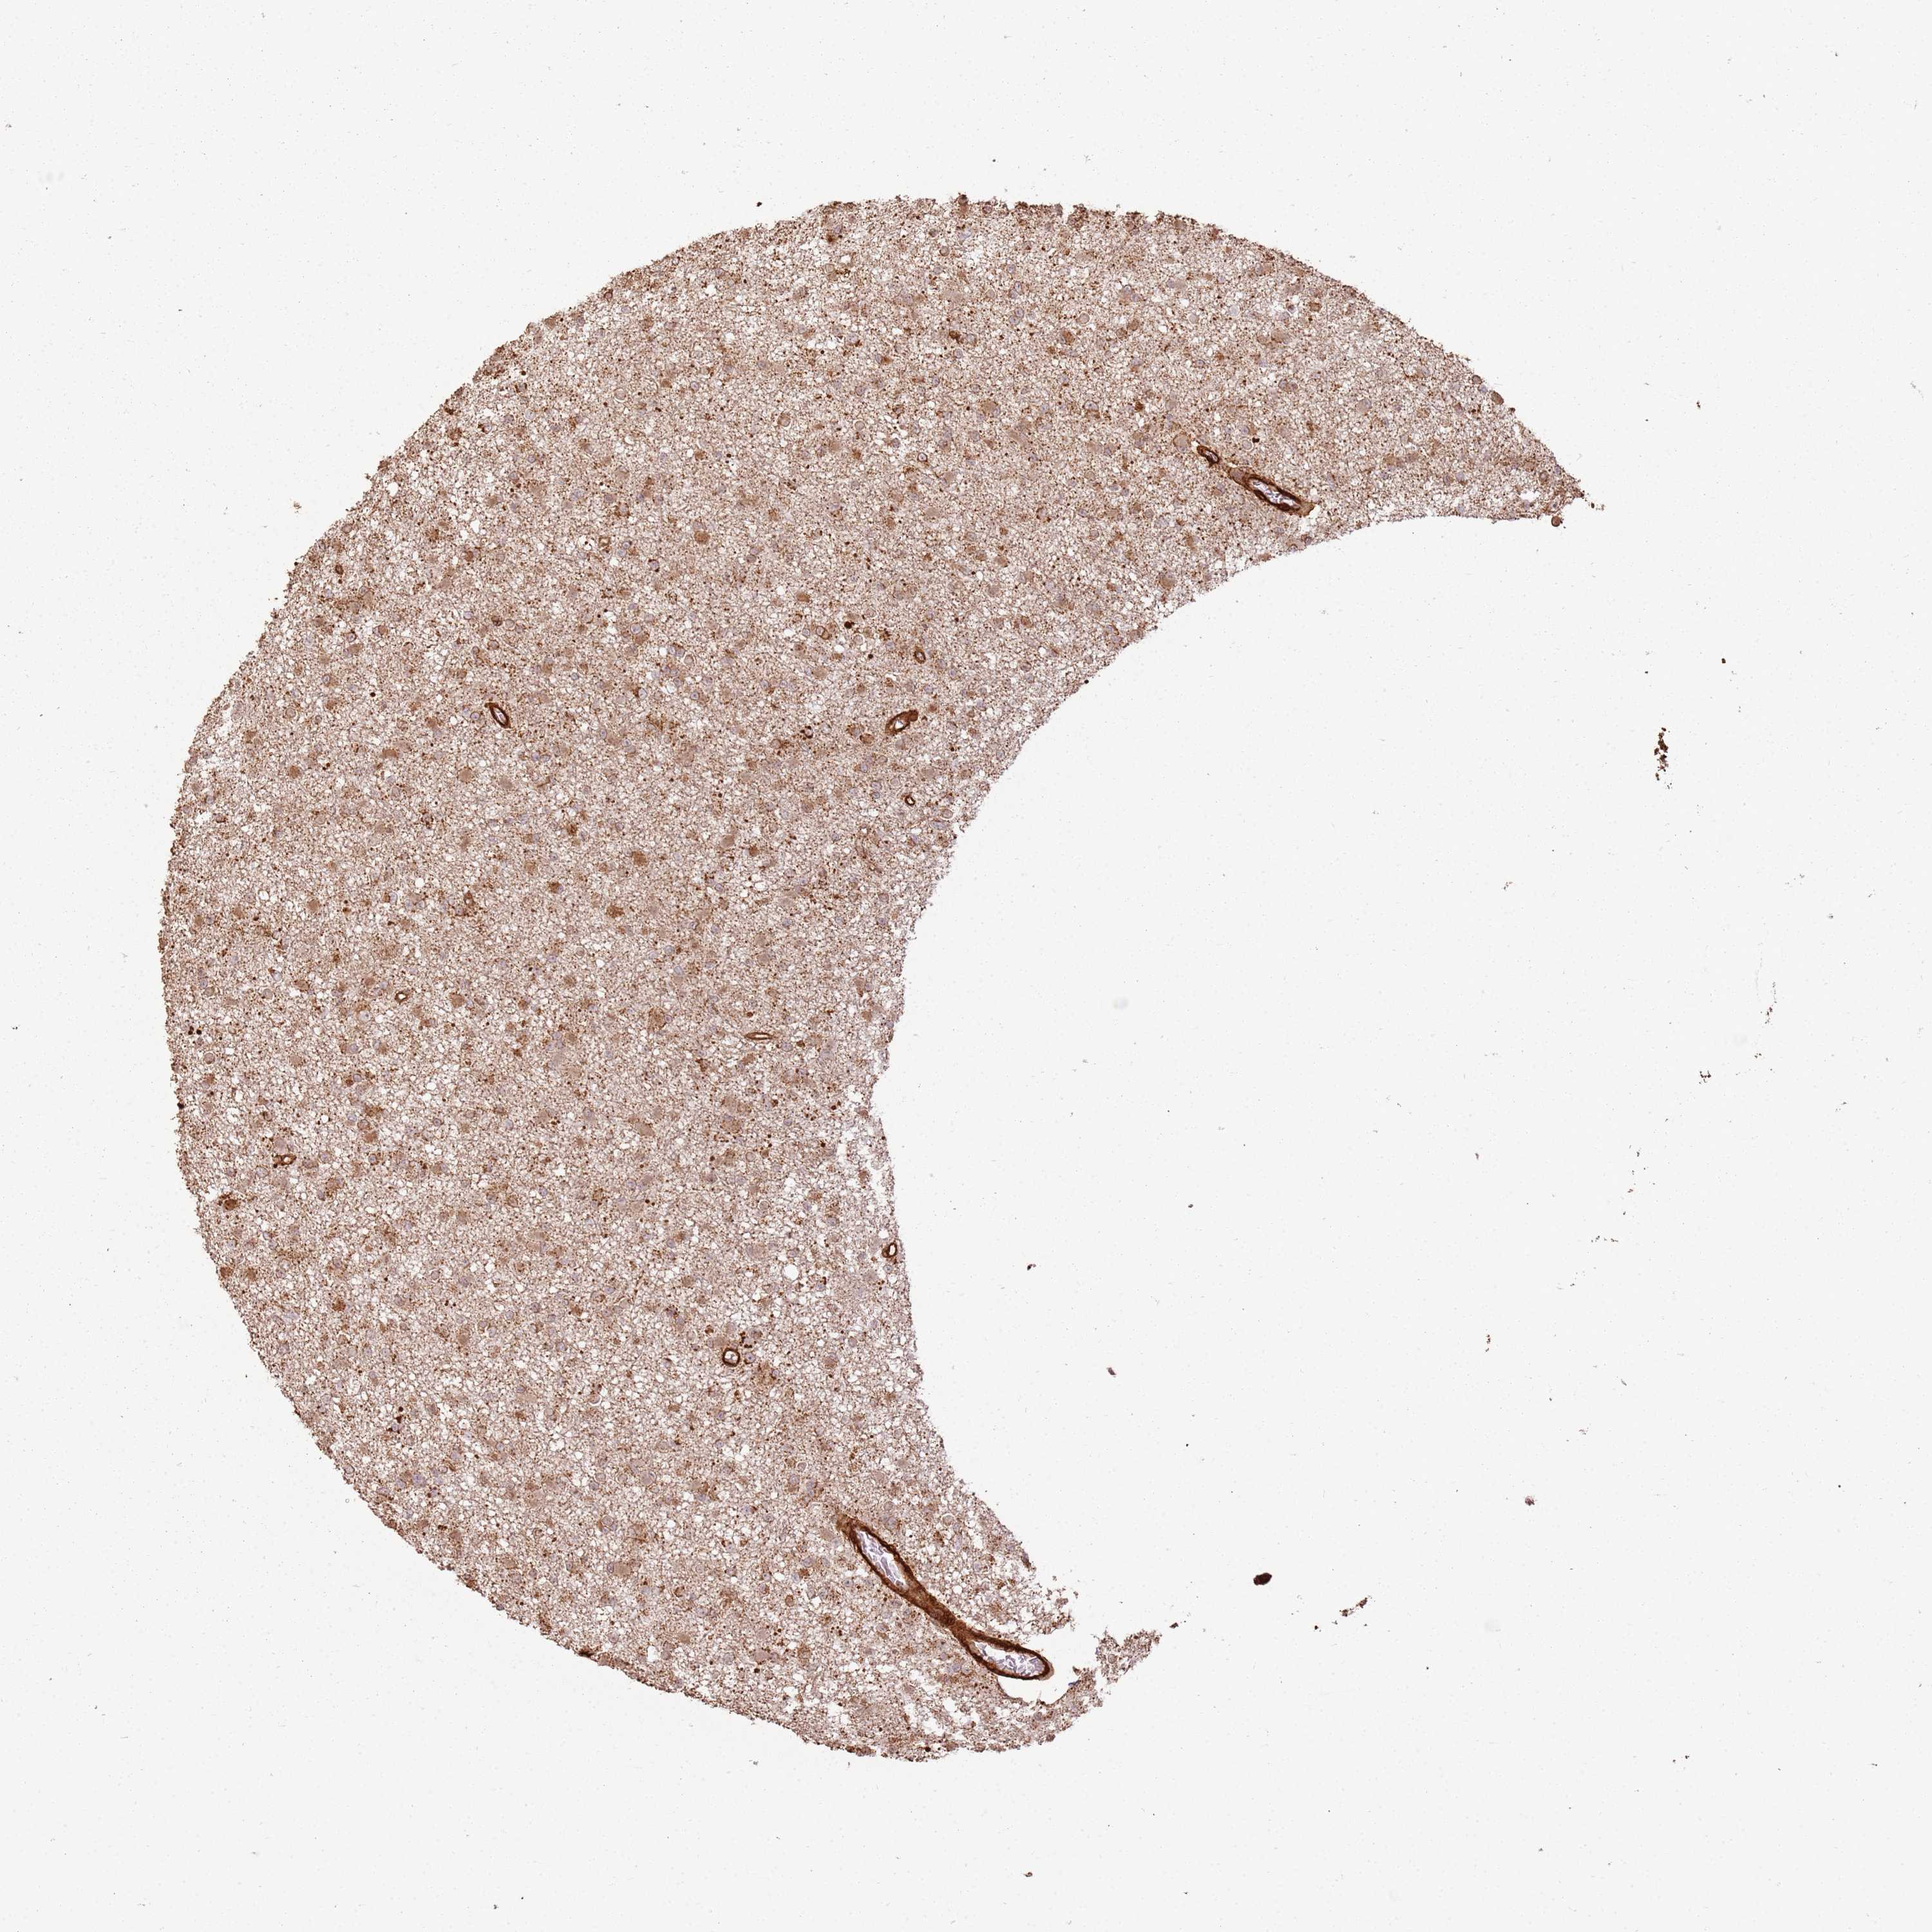

GLIOMA - Protein expressioni

A mouse-over function shows sample information and annotation data. Click on an image to view it in a full screen mode. Samples can be filtered based on level of antibody staining by selecting one or several of the following categories: high, medium, low and not detected. The assay and annotation is described here.

Note that samples used for immunohistochemistry by the Human Protein Atlas do not correspond to samples in the TCGA dataset.

Antibody stainingi

Antibody staining in the annotated cell types in the current human tissue is reported as not detected, low, medium, or high, based on conventional immunohistochemistry profiling in selected tissues. This score is based on the combination of the staining intensity and fraction of stained cells.

Each image is clickable and will lead to virtual microscopy that enables deeper exploration of all samples and also displays staining intensity scores, fraction scores and subcellular localization as well as patient and tissue information for each sample.

Antibody HPA047166

Staining

High

Medium

Low

Not detected

Intensity

Strong

Moderate

Weak

Negative

Quantity

>75%

75%-25%

<25%

None

Location

Nuclear

Cytoplasmic/membranous

Cytoplasmic/membranous,nuclear

Glioma, malignant, High grade

Glioma, malignant, Low grade